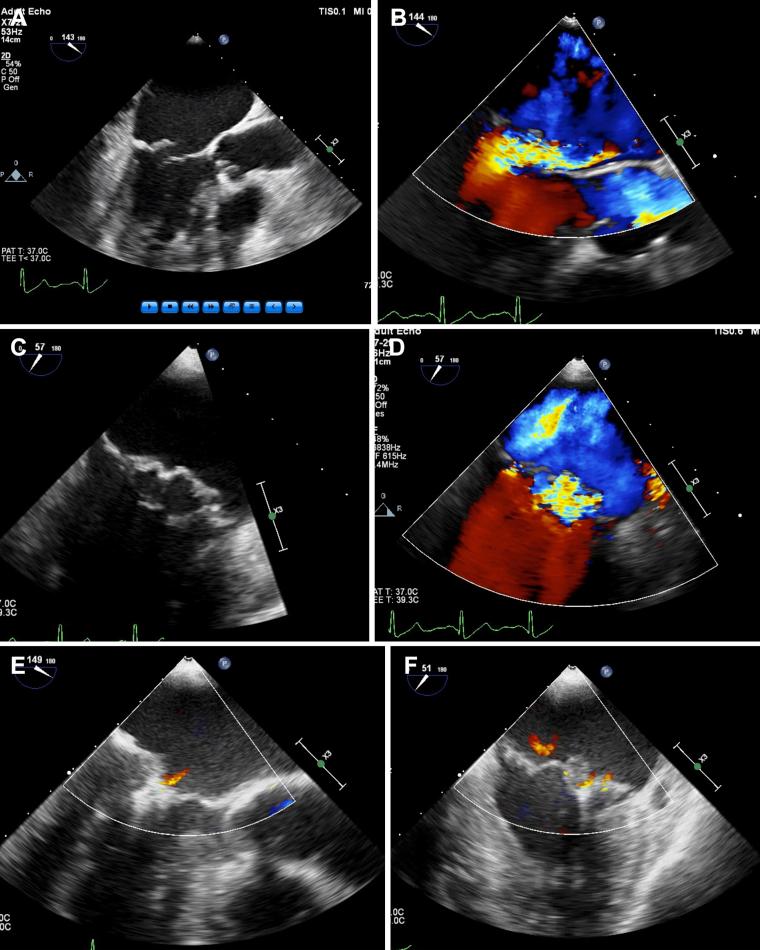

Transcatheter mitral valve repair using the MitraClip (Abbott Vascular, Santa Clara, CA) is a reasonable option for the treatment of patients with severe symptomatic degenerative mitral regurgitation (MR) who are at prohibitive surgical risk. The occurrence of recurrent severe MR after initial successful MitraClip repair is uncommon. Data are sparse on the management of recurrent severe MR after initial successful repair using the MitraClip. We describe a successful case of redo MitraClip repair for late recurrent severe MR secondary to progressive degenerative mitral valve disease after a successful initial MitraClip procedure and review the literature.